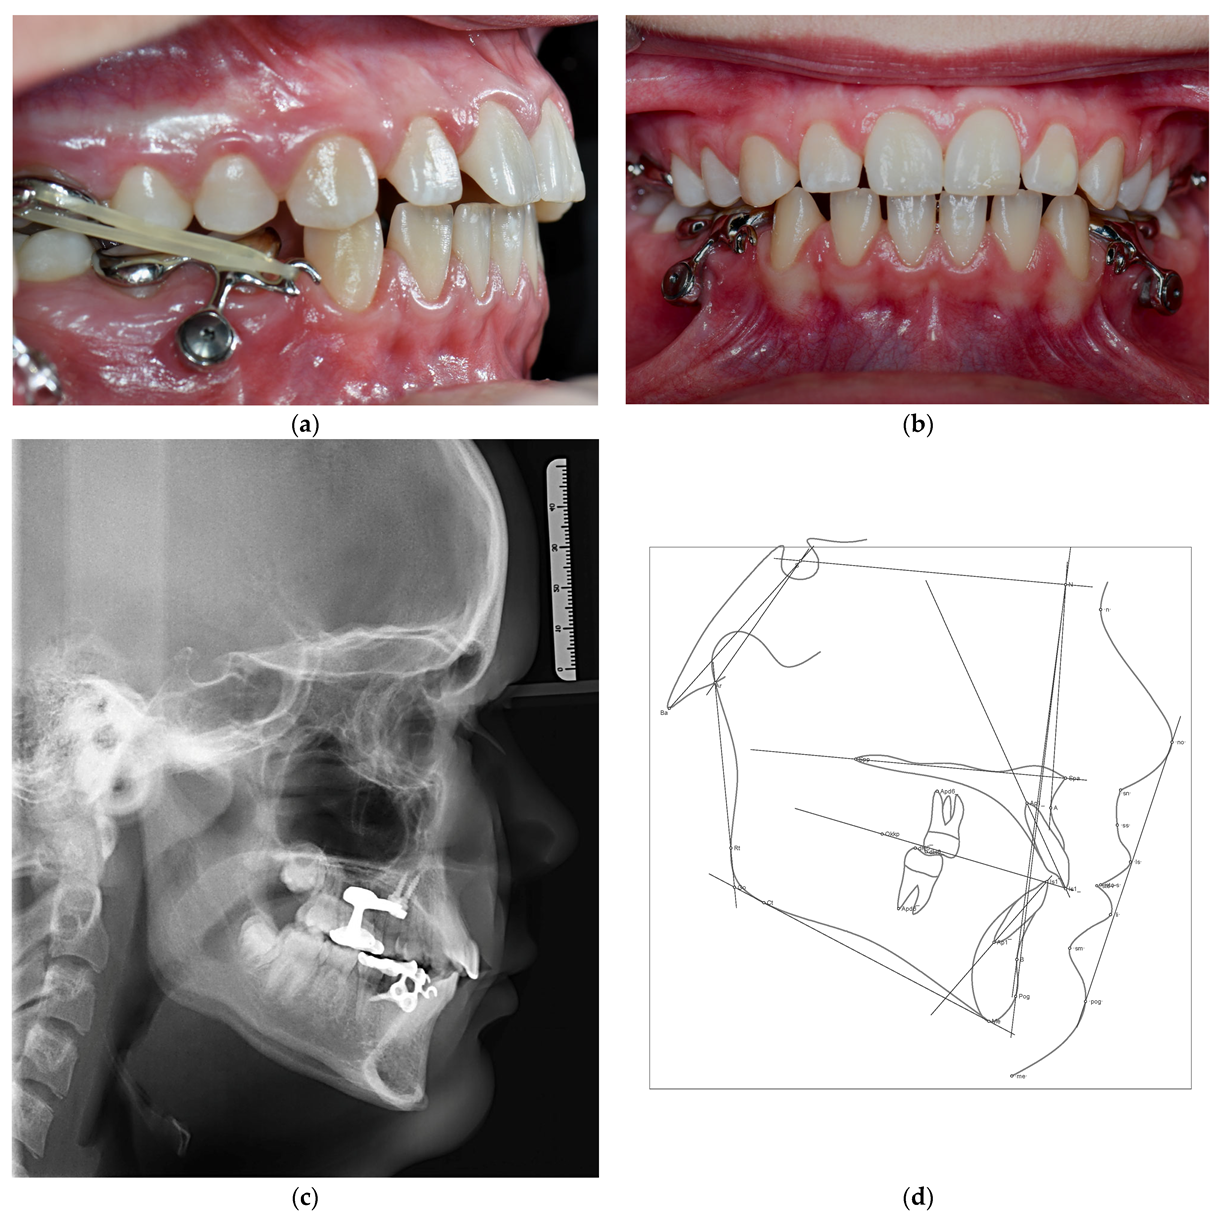

2. Diagnosis

3. Treatment

3.3. Treatment Progress